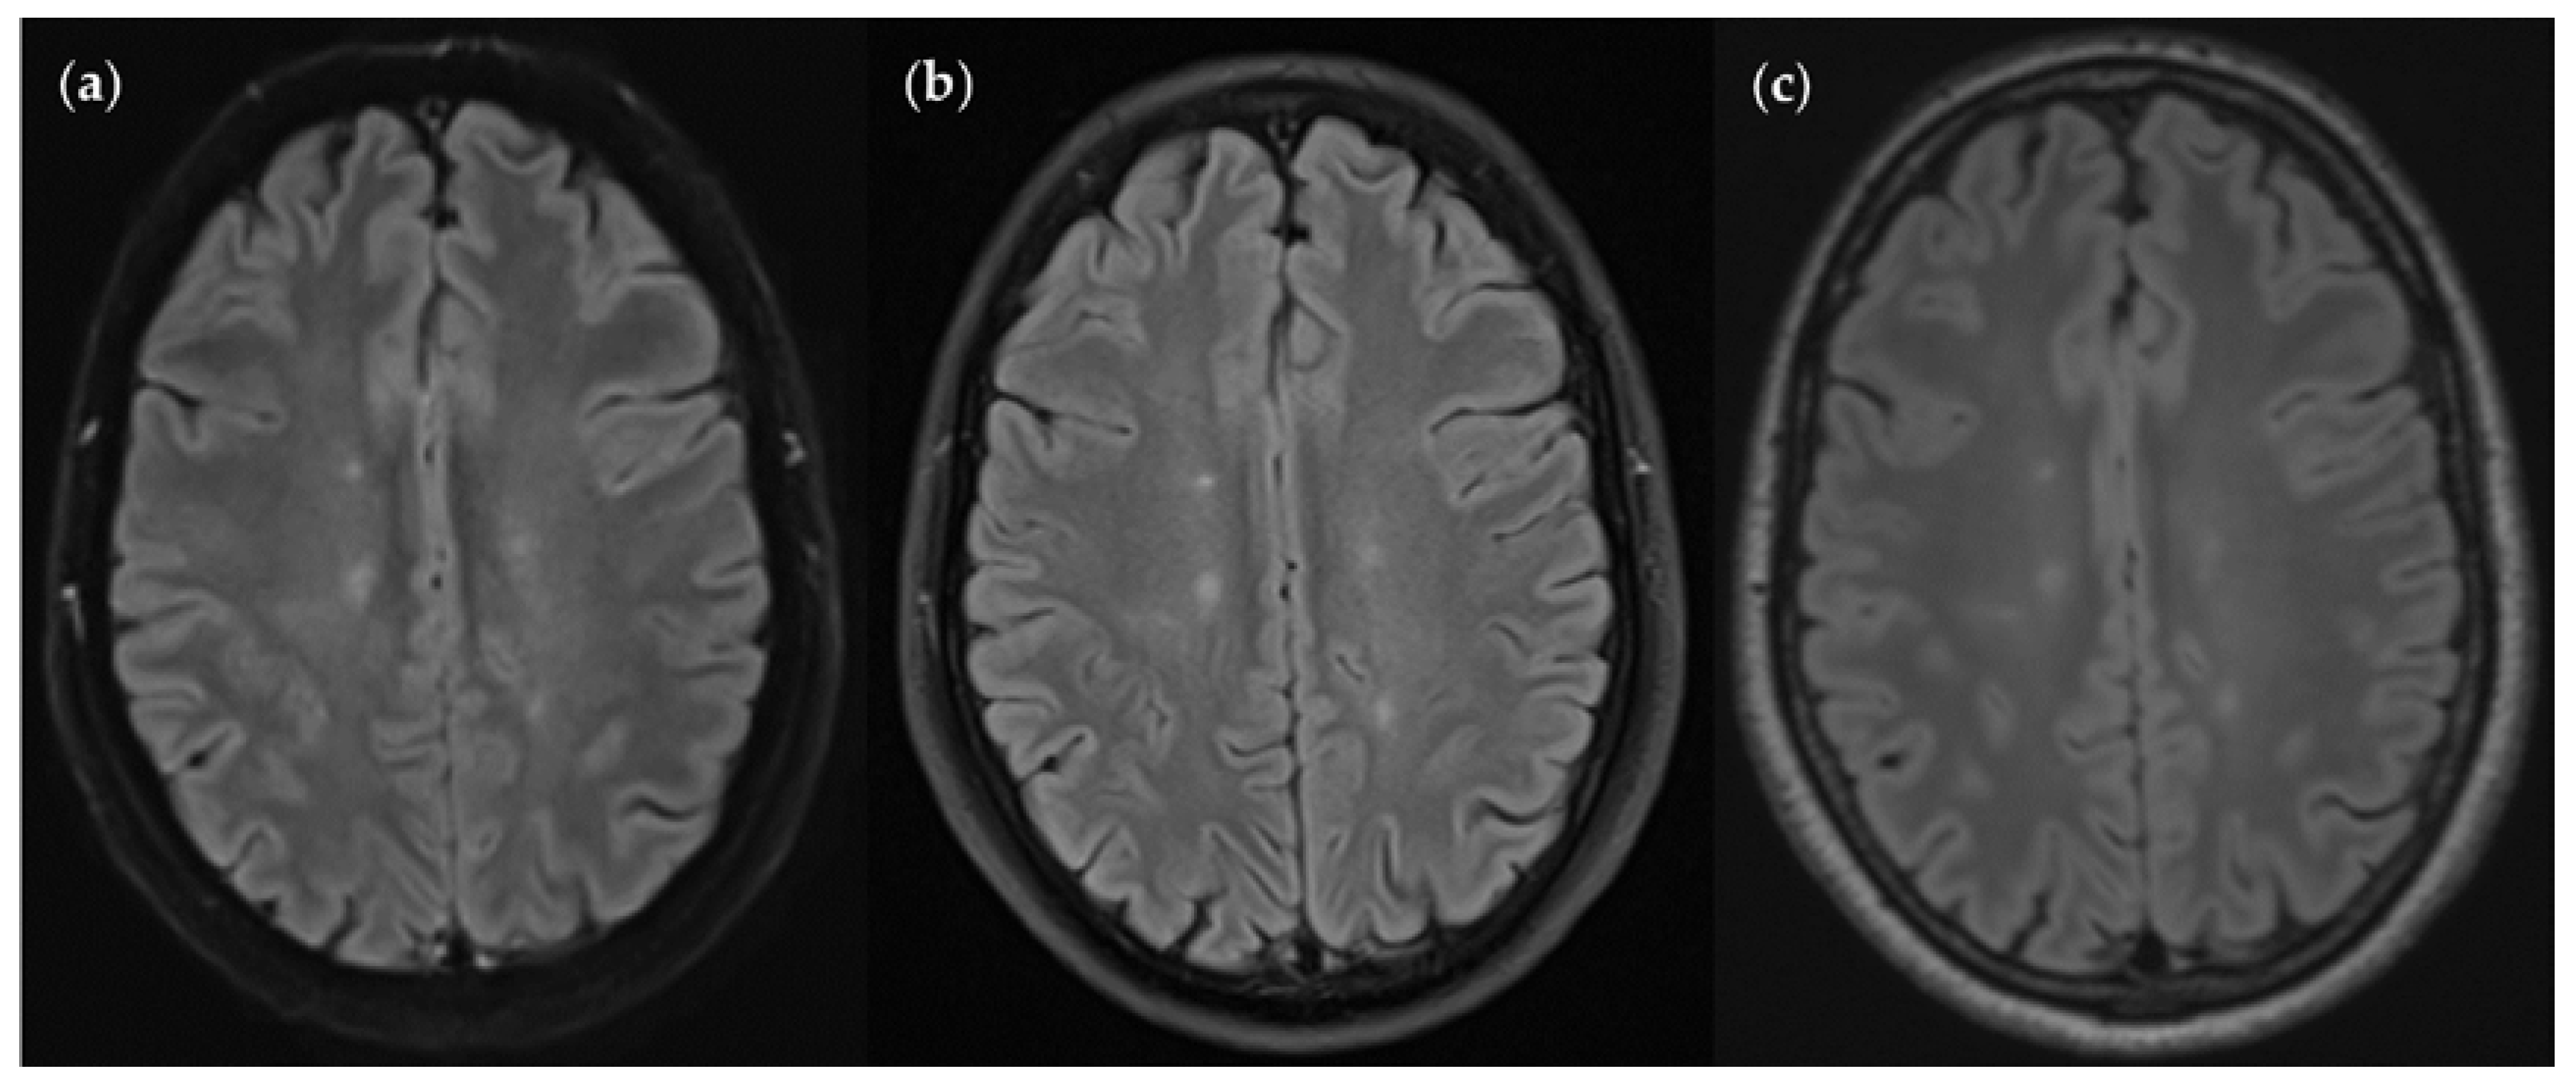

An MS patient received an MRI scan including three T2w FLAIR sequences: FLAIRUF (a), FLAIRTSE (b) and FLAIR3D (c). Five lesions can be seen in each picture, situated in the frontoparietal region.

Figure 10.